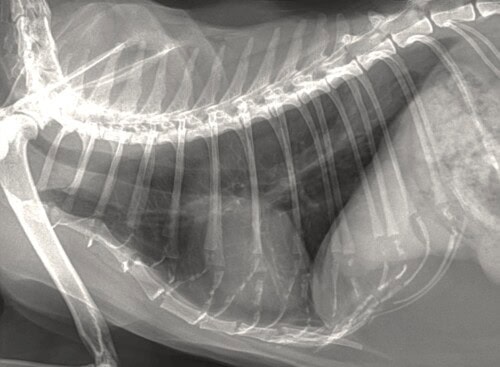

– de ce fait, des radiographies thoraciques sont décidées et ne montrent pas d’anomalie notable.

Photos 4 et 5: Radiographies thoraciques (profil et face dorso-ventrale)

La récupération post-opératoire est bonne et la chatte remarche normalement. Une nouvelle radiographie thoracique au retrait des fils ne met toujours pas en évidence de lésion pulmonaire primitive.

De nouvelles radiographies révèlent alors des lésions ostéolytiques identiques de la dernière phalange de ce doigt III de l’antérieur droit, mais surtout la présence d’une masse tissulaire dans les lobes caudaux, compatible avec une tumeur pulmonaire. Aucun signe respiratoire n’est présent.

Photo 10 : Radiographie thoracique de profil droit.

Présence d’une masse pulmonaire dans les lobes caudaux